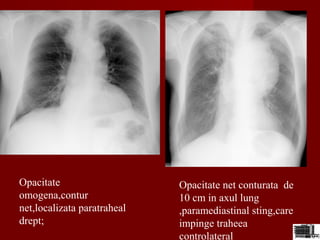

Opacitate

omogena,contur

net,localizata paratraheal

drept;

Opacitate net conturata de

10 cm in axul lung

,paramediastinal sting,care

impinge traheea

controlateral